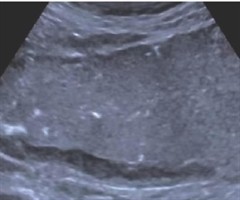

肠道超声在慢性腹痛或腹泻患者临床诊断中的应用价值

摘要:目的评估肠道超声(IUS)对慢性腹痛或腹泻患者肠道器质性病变的诊断价值。方法回顾性分析263例慢性腹痛或腹泻患者的IUS 征象,以内镜检查结果为金标准,比较内镜阳性组与阴性组之间的IUS 征象差异,以及阳性病例中的炎症性肠病组与肠道非...